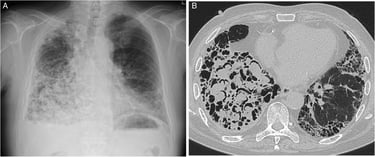

Micosis broncopulmonar: El hongo intenta colonizar los tejidos húmedos de los pulmones.